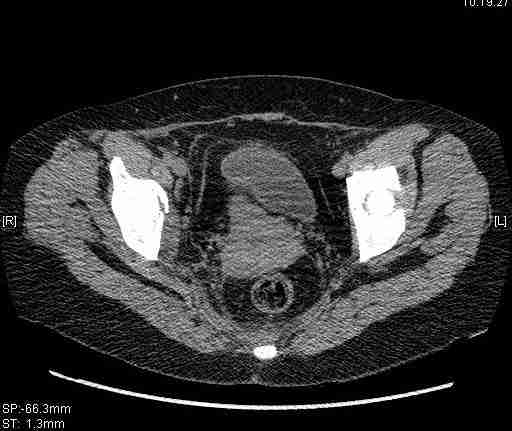

Удалось сегодня вывести пациентку в соседнюю больницу, где есть кт. Срезы сделаны только горизонтальные.